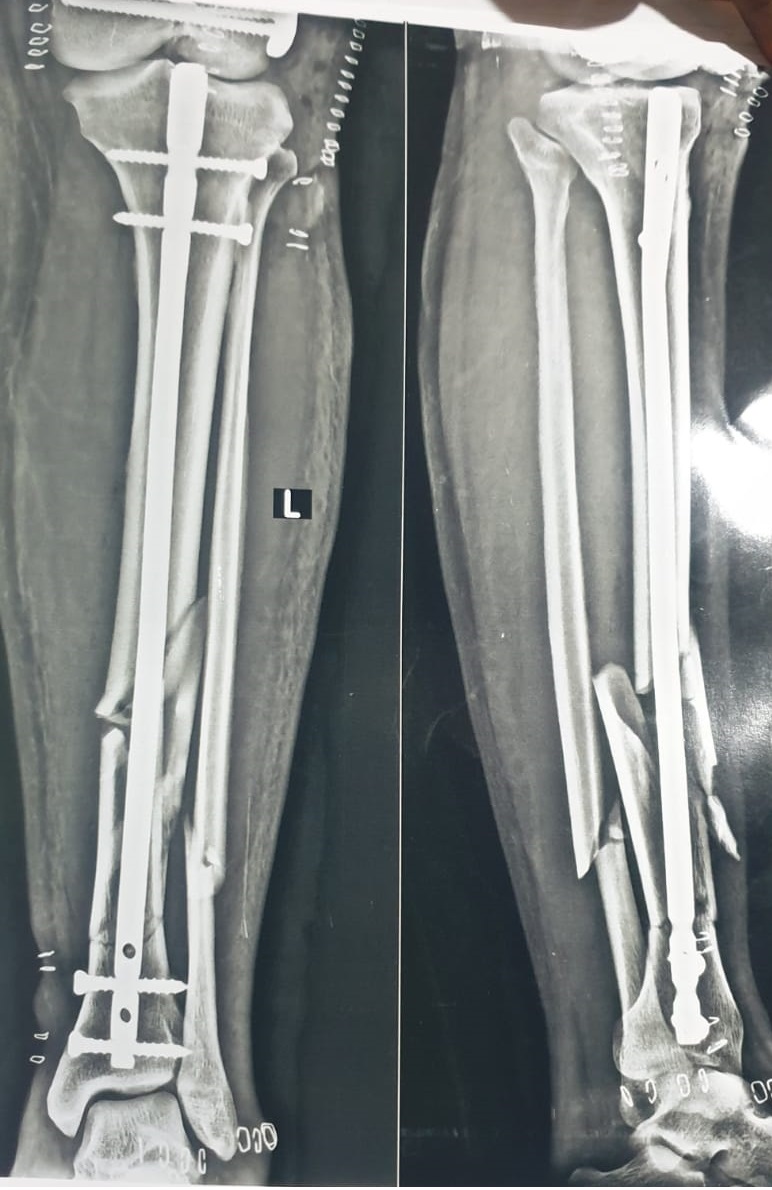

A precise entry point was created at the proximal tibia, and a guidewire was advanced under fluoroscopy. After preparing the canal, Samay Surgical Pvt. Ltd.’s Expert Tibia Nail was inserted to realign and stabilize all fracture segments. Proximal and distal locking screws secured the construct, restoring length and rotational control. Final imaging confirmed perfect positioning, and the incision was closed, completing a smooth and efficient procedure.

The patient was monitored for swelling, pain, and circulation, with early physiotherapy started to maintain joint movement. Weight-bearing was introduced in stages as healing progressed and X-rays confirmed stable fixation around the Expert Tibia Nail. Overall recovery remained smooth, with steady improvements in mobility and comfort.

3. Recovery usually takes 10–14 weeks, and the use of Samay Surgical’s precision-engineered orthopedic implants supports stronger fixation and smoother rehabilitation.

Implant Material Size

Expert Tibia Nail Titanium GR.5 10mm*300mm

Interlocking Screw Titanium GR.5 4.3mm*30mm

Titanium GR.5 4.3mm*32mm

Titanium GR.5 4.7mm*34mm

End Cap Titanium GR.5 5mm